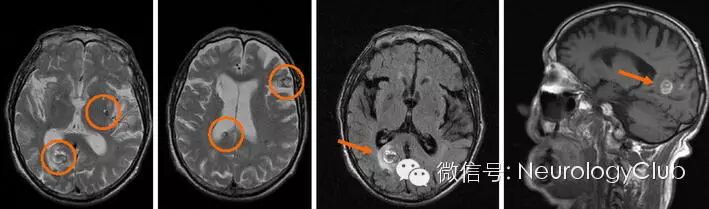

(CT提示右侧枕部,邻近右侧脑室三角区,透明隔和左侧额部多发高密度病灶

(MRI证实右侧枕区出血性病变伴灶周T1高信号以及内部混杂信号的多发海绵状血管瘤)